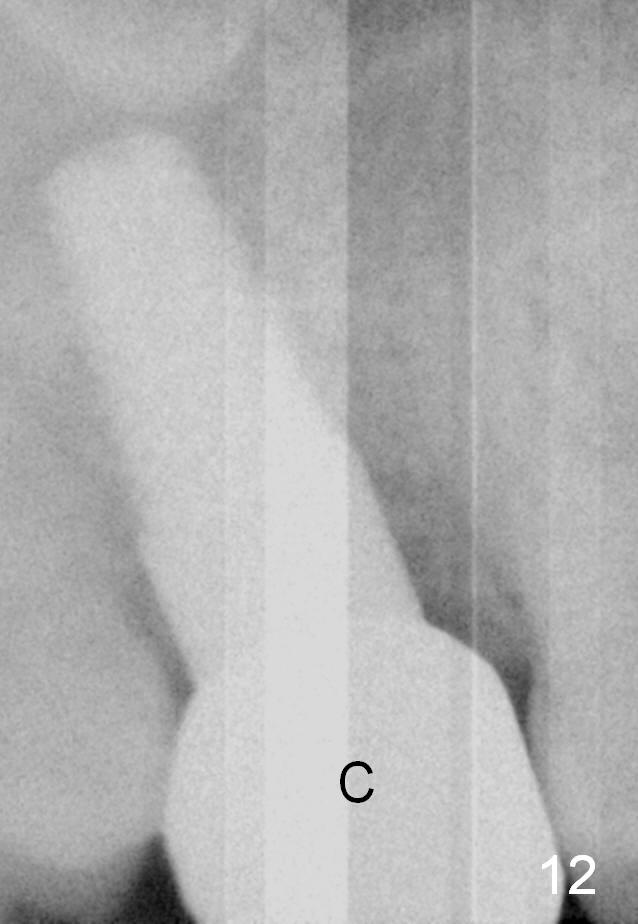

The implant remains stable 2.5 months postop without abnormal bone resorption (Fig.9). Since the provisional has dislodged on several occasions, impression is taken for final restoration. When the provisional is removed 3 months postop, the margin of the restoration is shown to be subgingival (Fig.10 arrowheads), but is distinctly separated from the gingiva. This is due to the presence of the provisional (its margin were fabricated slightly deeper). The provisional is also intentionally fabricated slightly larger than the final restoration. When the latter is cemented, there is space to remove extra cement trapped subgingivally (Fig.11). No cement is visible post cementation (Fig.12 (C: crown)). Eighteen months post cementation, the patient returns for recementation. After laser gingivectomy and Panavia resin bonding, PA shows residual cement (Fig.13 ^). After repeated removal with Piezo scaler and explorer, the residual cement appears to be smaller, which is ignored at the time of X-ray taking (Fig.14 ^). More dismayed is tight mesial contact. Water pik is recommended. When peri-implantitis develops later on, make an incision for cement removal. If the crown is dislodged soon, check whether the existing abutment is loose, remove acrylic in the access hole and remove the abutment. Install a new 4x3 mm one. Trim the abutment carefully and more on the opposing tooth.